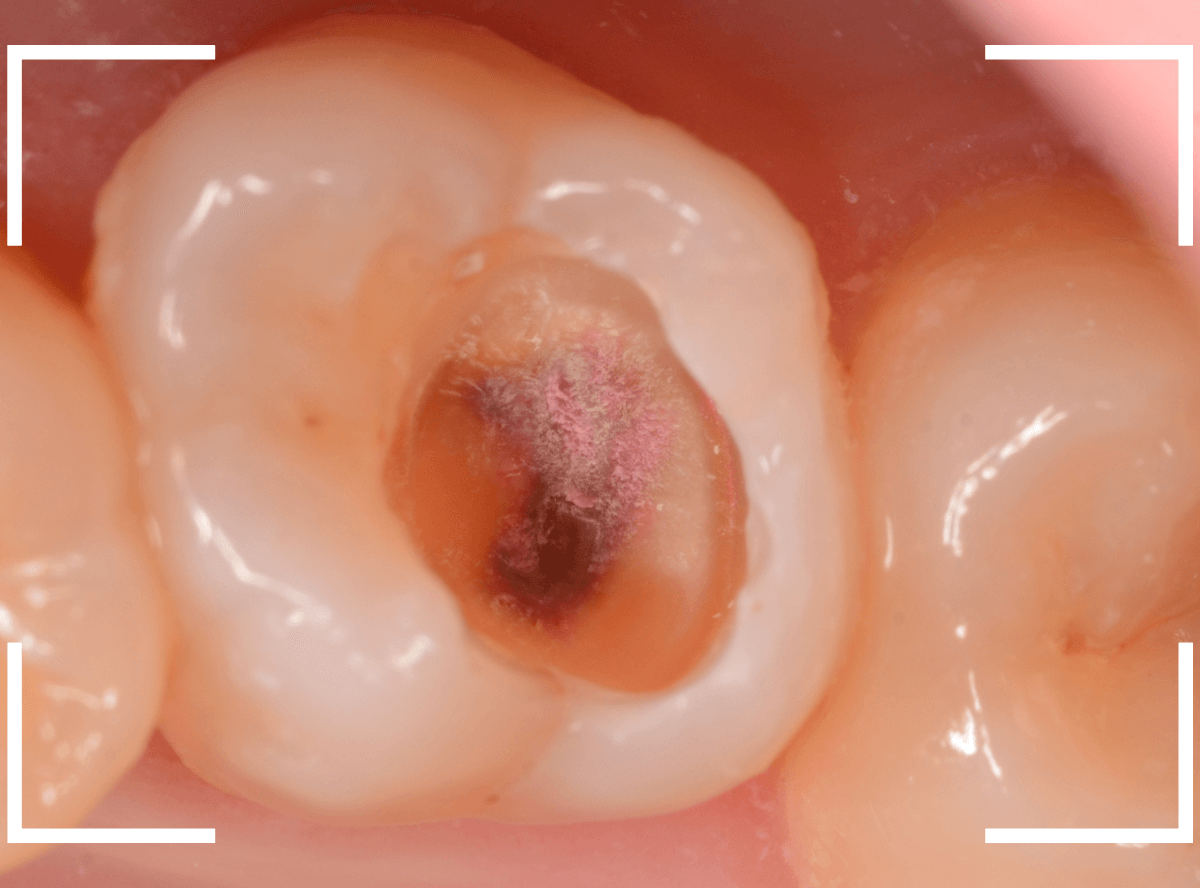

Case.12 仮つめ中のレジンの下がひどい虫歯

今回は、他院で治療途中で離脱後、放置してしまった患者さんの例です。

一目瞭然かと思いますが、仮つめ?にしていたレジンがかけて、中が虫歯になっています。

レントゲン写真で確認します。

青い部分が歯の神経で、赤い部分が虫歯です。

神経寸前まで虫歯が進行しているのがわかります。

ここまで虫歯が進行していたら、何か症状が出てもおかしくないのですが、特に症状はないそうです。

本人にYAVAY状況を説明して、早急に治療を開始します。

レジンを除去すると、すぐに大きな虫歯が見えてきました。

赤い部分が虫歯です。

今にも神経が見えてしまいそうで怖いです。

エキスカを使って、少しずつ虫歯を除去します。

ほぼ、全ての虫歯を除去したところです。

〇部が神経の入り口です。

ここをお薬で保護し、セメントで蓋をしてしばらく様子をみます。

痛みが出て取れなけば・・・改めて神経を取る治療が必要になります(>_<)